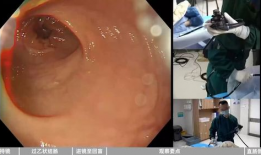

肠镜怎么做的过程视频,直观视频带你了解每一步

最近是不是听说肠镜检查这个词儿,心里直打鼓?别担心,今天就来给你揭秘肠镜检查的全过程,让你对它有个直观的了解。咱们先来个热身,想...